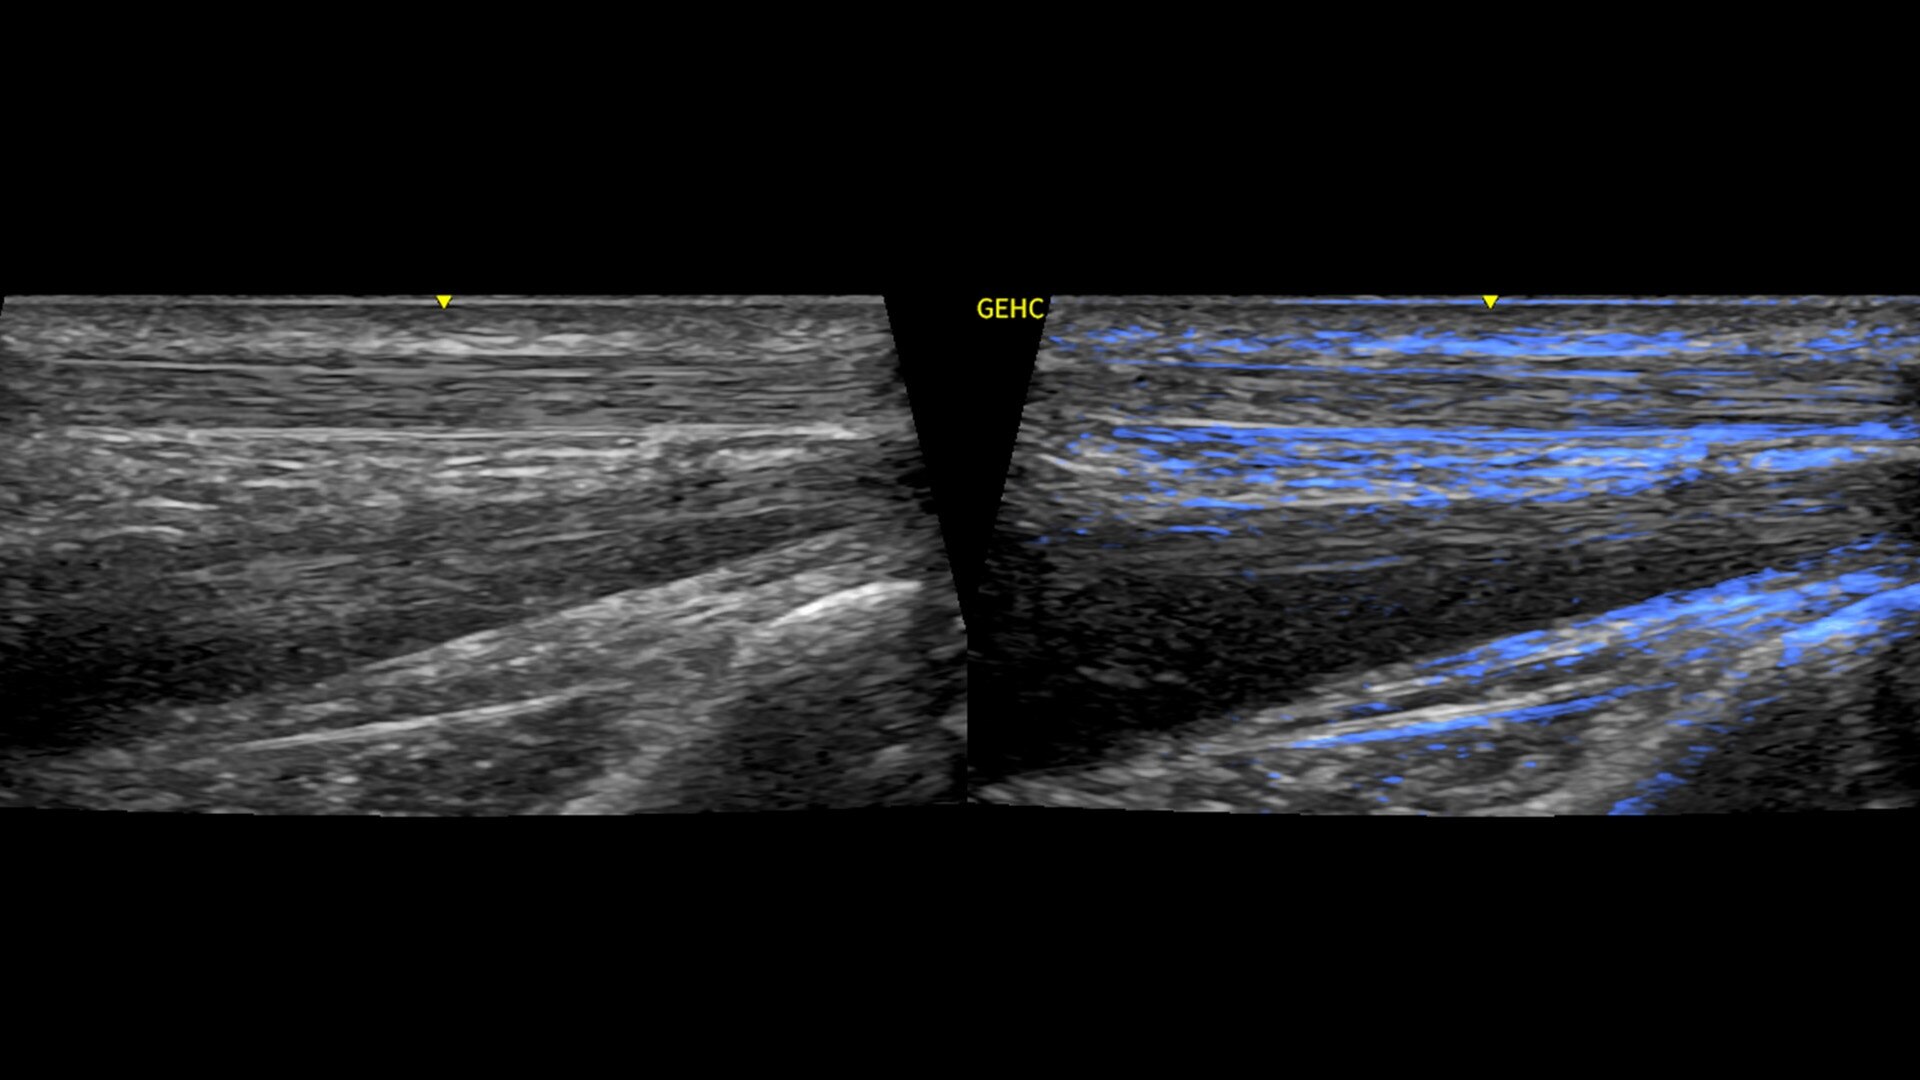

• Optimize images while scanning with Whizz clinical features, easily improve Color Doppler with Whizz Color Flow, and view scans in the image style that suits your preference with Whizz Easy Style

Verisound™ Collab** is a virtual collaboration tool that easily extends your team's expertise with real-time connections throughout your network.

• Collaborate - Easily share the expertise of your highly skilled team with real-time collaboration throughout your network

• Connect - Your team can connect with others before, during and after an exam to gain real-time support when you need it

• Care - Help improve users' ability to confidently and efficiently perform exams